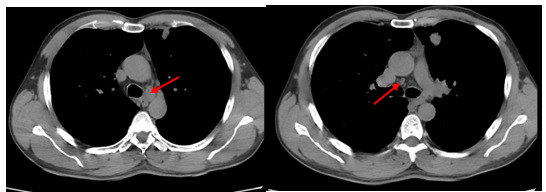

- Chụp cắt lớp vi tính lồng ngực: phim trước điều trị

Hình 1. Trên phim chụp CT lồng ngực ở cửa sổ nhu mô: thùy trên phổi trái có khối đặc tròn bờ tua gai, kích thước: 29 x20mm, kính mờ và dày kẽ xung quanh, lân cận có nốt bán đặc kích thước 29 x 17mm, ngấm thuốc không đồng nhất sau tiêm, nghi ngờ có phần xâm lấn trung thất trước. Nhu mô thùy còn lại và nhu mô phổi phải lan tỏa các nốt đặc tròn to nhỏ không đều, đường kính: 2-8mm.

Hình 2. Cửa sổ trung thất: Vài hạch trung thất cạnh khí, hạch lớn nhất kích thước 14x7mm

- Cắt lớp vi tính lồng ngực:

Sau 3 tháng điều trị đích:

- U nguyên phát và u thứ phát ở cả 2 phổi đều giảm kích thước rất nhiều, không thấy hạch trung thất.

Sau 6 tháng điều trị:

- U nguyên phát chỉ còn kích thước rất nhỏ, u thứ phát 2 bên phổi đã mất hết.